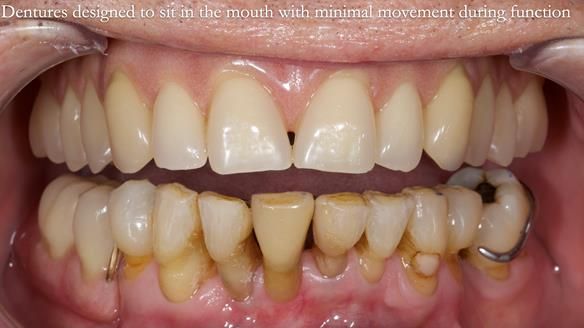

Welcome to my Newsletter 54 showing the making and fitting of dentures (a complete upper metal reinforced denture, a lower immediate partial denture and a definitive Scandinavian designed, metal based lower partial denture) for David, a 75 -year-old man. The full protocol workflow is presented including the use of dentate photographs to mimic his natural teeth.

- Current complete upper denture had many technical problems. Poor retention, support, stability and tissue fit.

- Missing teeth on the lower right side. This makes the upper denture tip when chewing and biting.

- The remaining lower 9 teeth had periodontal disease. Syed Abad, Specialist in Periodontics at the practice managed it.

Interestingly we found that the upper complete denture when finished and fitted didn’t have good enough retention for David’s satisfaction. It was relined by adding compound to the buccal flanges – to almost overextend into the sulcus to ‘create’ a sulcus, followed by using a light bodied silicone impression material. This improved the function of the C/-considerably. A lower Scandinavian hygienically designed lower RPD was also provided which helped with occlusal stability and reseating the upper denture – further improving the fit.